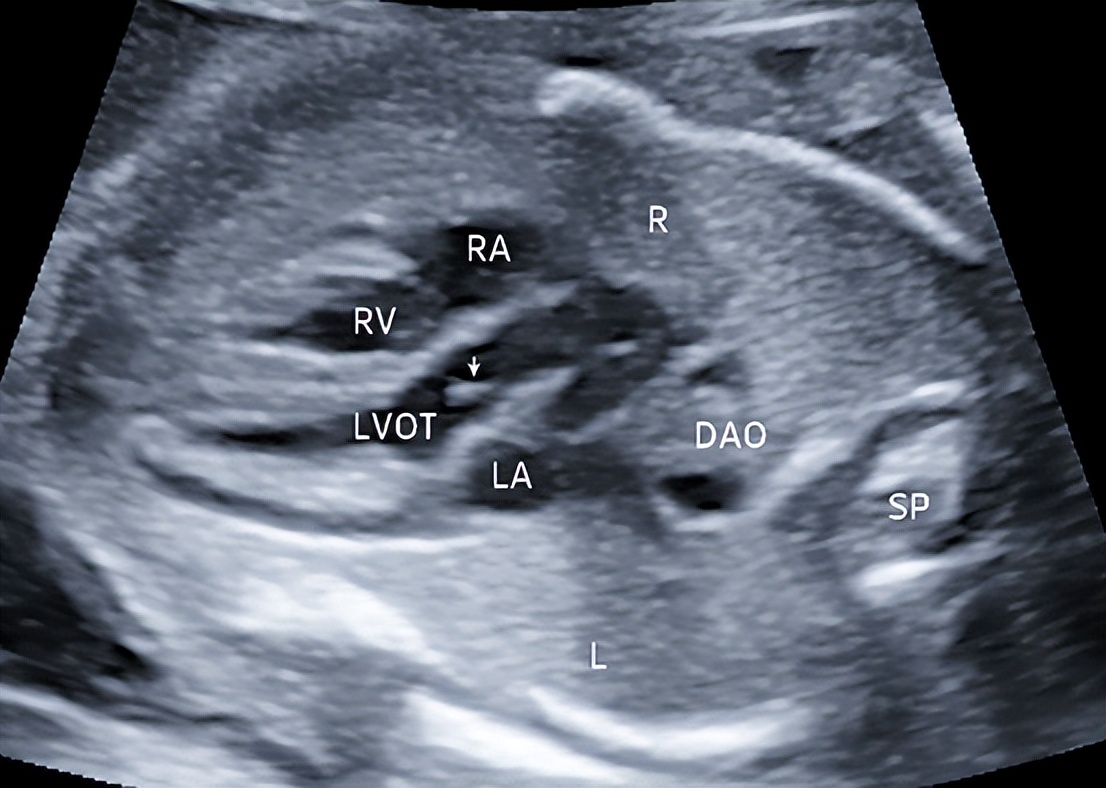

2.左心室流出道切面

切面要求:显示左心室及起自左心室的主动脉和主动脉瓣(图2)。

观察内容:主动脉前壁与室间隔相连续,后壁与二尖瓣呈纤维性连接,起自左心室后向右上方走行,与肺动脉呈交叉走行,内径略窄于肺动脉,主动脉瓣启闭自如。

图2 孕23周左心室流出道切面 显示左心室及起自左心室的主动脉,箭头所示为处于关闭状态的主动脉瓣(LA:左房;RA:右房;RV:右室;LVOT:左心室流出道;DAO:降主动脉;SP:脊柱;L:左侧;R:右侧)